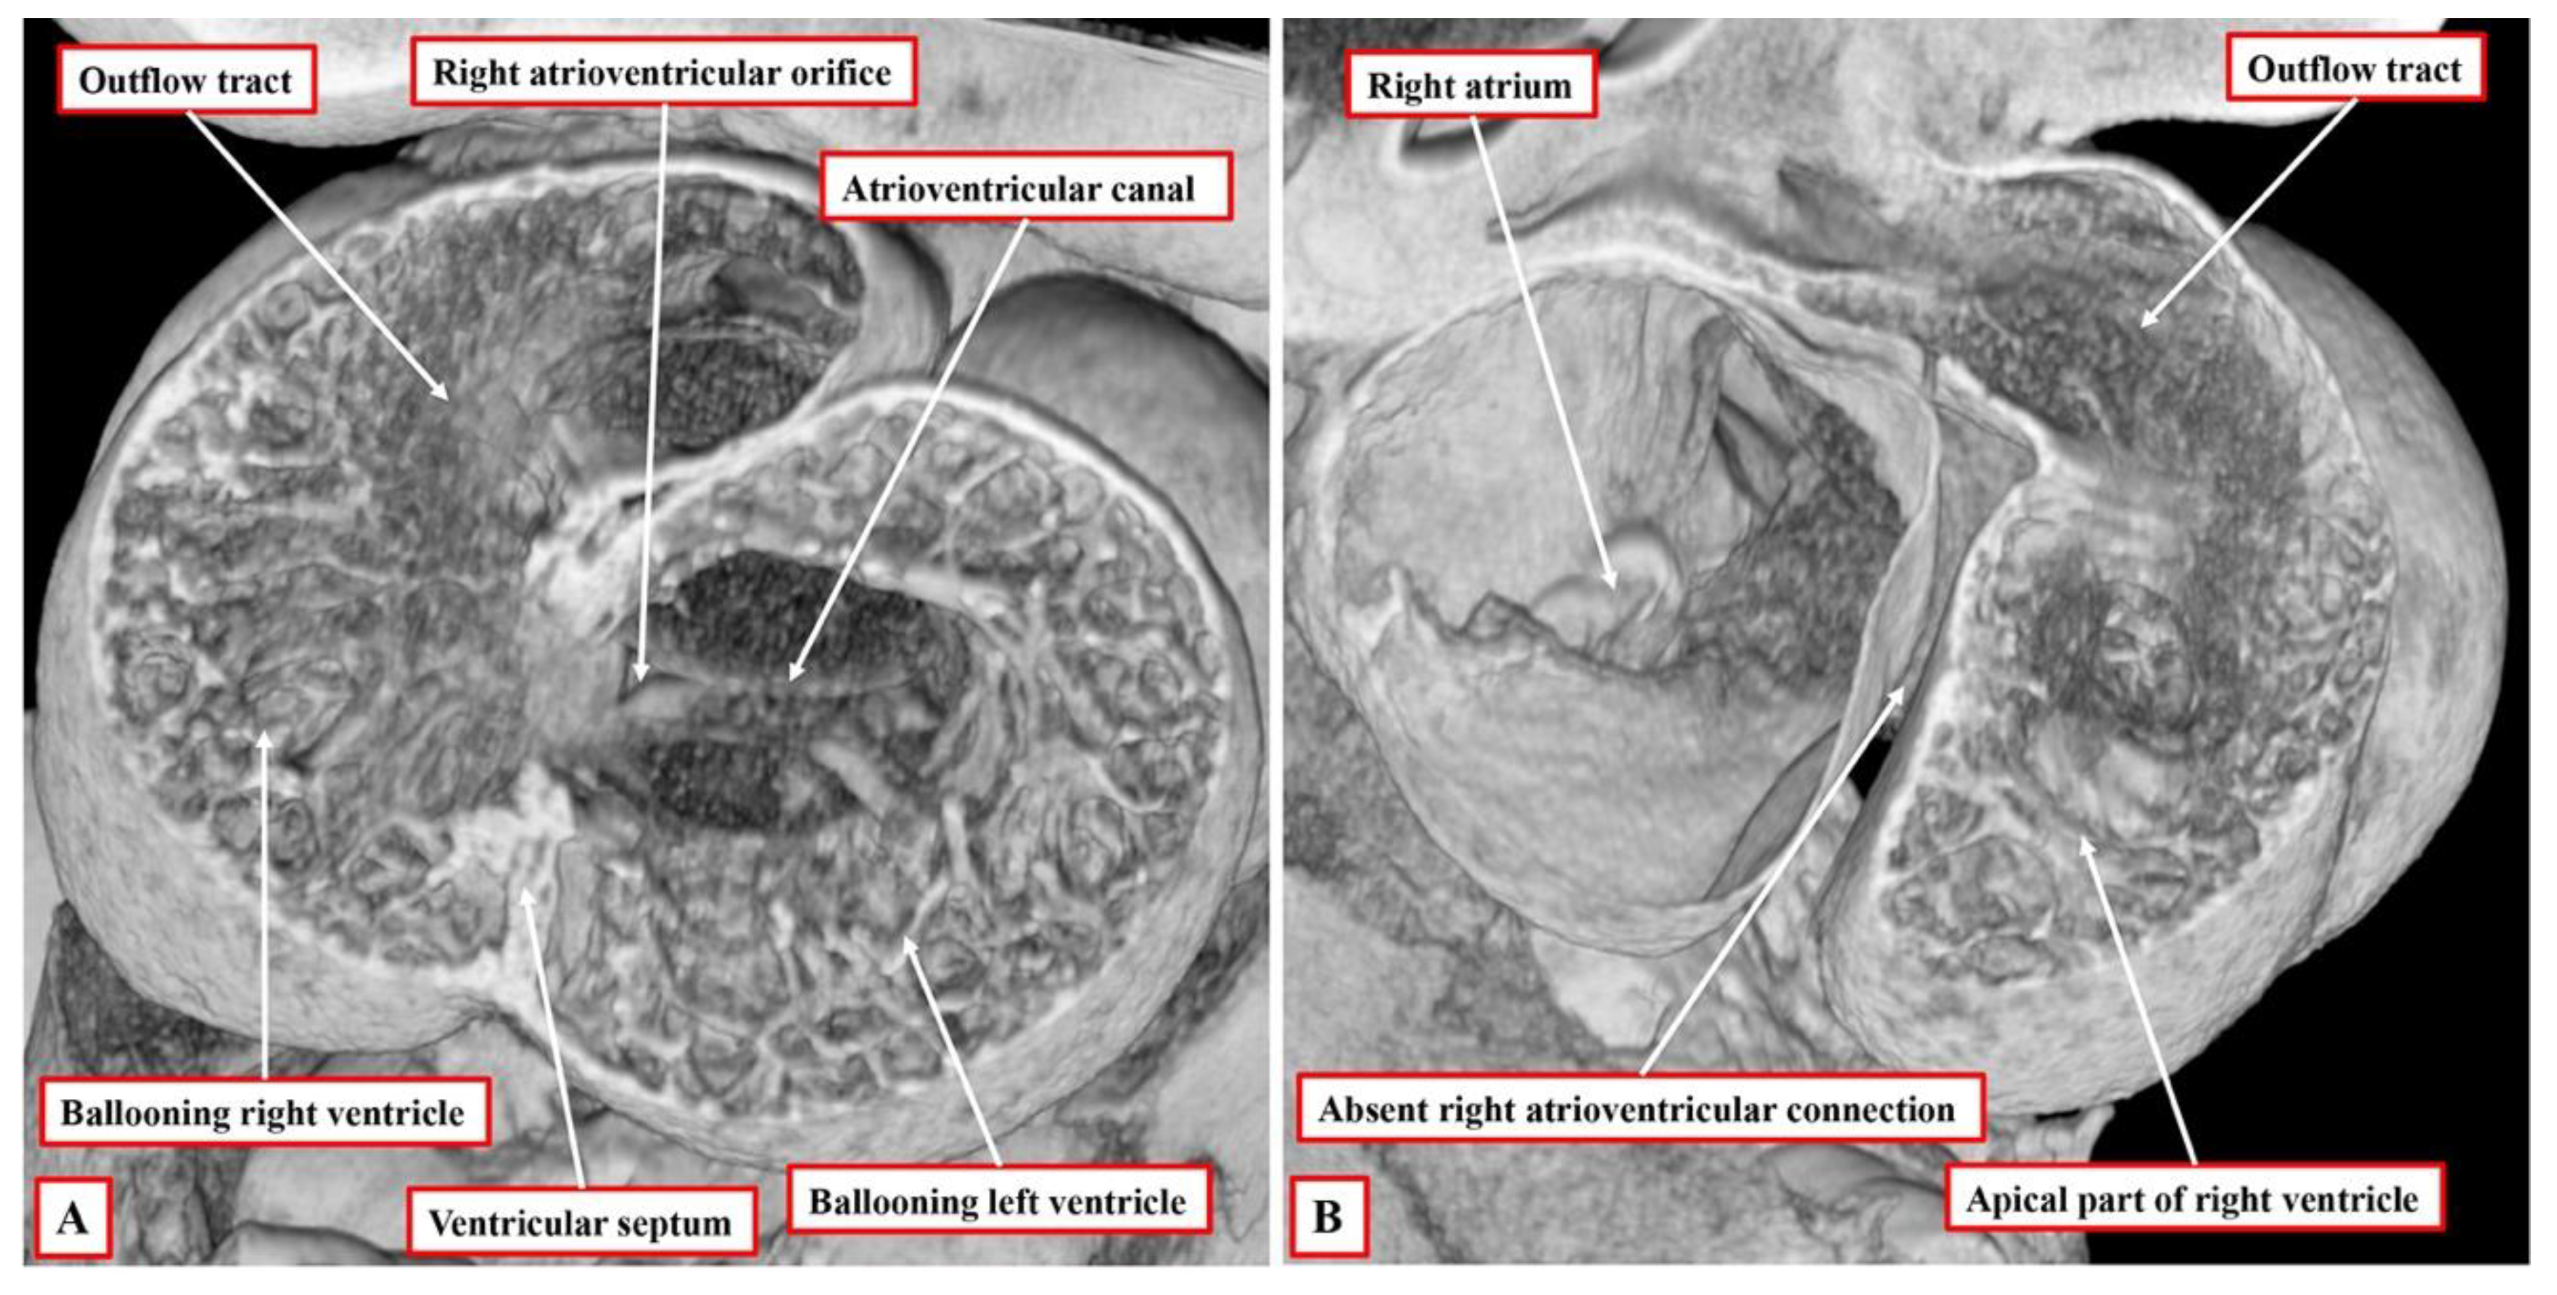

11]. Having looped, the ventricular component of the developing heart initially remains a tube, but with obvious inlet and outlet components. At this initial stage, the inlet part of the loop supports the entirety of the circumference of the atrioventricular canal, whereas the outlet part supports the entirety of the developing outflow tract. Shortly after completion of the process of looping itself, the apical ventricular components can be seen “ballooning” from the outer curvature of the loop, with the left ventricle developing from the inlet part, and the right ventricle developing from the outlet part (

Figure 2A).

The arrangement at the early stage is pertinent to the commonest variant of tricuspid atresia, which is shown in

Figure 1. Since the right side of the atrioventricular orifice opens into the developing left ventricle, the developing right ventricle lacks a direct atrial input (

Figure 2B). In consequence, the developing right ventricle, at this early stage, is incomplete, possessing only apical and outlet components. The left ventricle, in turn, possesses only inlet and apical components. At this early stage, therefore, it is not possible to determine with precision the topological arrangement of the ventricle mass. The relationship of the incomplete right ventricle to the dominant left ventricle could be changed simply by rotating the heart itself.

It is the next stage of development that sets the scene for the establishment of ventricular topology. Simply by expansion of the atrioventricular canal, the right ventricle achieves its own inlet component. In the murine heart, this process occurs between embryonic days 10.5 and 11.5 (Compare

Figure 2 and

Figure 3). In the human heart, the period encompasses the fifth and sixth weeks of development subsequent to fertilisation. Once it has achieved its own inlet (

Figure 3A), even though it continues to support the entirety of the outflow tract, the right ventricle can be recognised to have achieved right-handed topology (

Figure 3B). It is the morphologically right ventricle, by convention, that is used as the arbiter of ventricular topology or chirality. The concept depends on the ability, figuratively speaking, to place the palmar surface of the hands on the septal surface of the right ventricle. The thumb is placed in the tricuspid valve, the wrist occupies the apical trabecular component, and the fingers extend into the ventricular outflow tract. In the normal heart, once the right ventricle has developed its own inlet (

17]. There are multiple flaws in the logic underscoring this suggestion, not the least that, if the chamber were truly no more than an infundibulum, it would not be possible to diagnose transposition, which requires the aorta to arise from the morphologically right ventricle or its rudiment. As we have already shown, the evidence is now overwhelming from cardiac development that, from the outset, the small chamber in hearts with a dominant left ventricle possesses an apical trabecular component of right ventricular morphology (

Figure 2B).